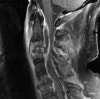

3. MRI

-

정확하고 빠른 효과적인 진단 수단

단, pyogenic과 non-pyogenic infection을 감별할 수 없으므로 조직 생검의 필요성을 줄이지는 못합니다.

추체와 그 사이의 추간강 부위는 T2 강조영상에서는 신호강도 증가, T1 강조영상에서는 신호강조 감소되어 경막 외 확장이나 연부조직 농양의 윤곽을 나타내는 데 유용합니다.

MRI : 척추 감염(Spinal infection)